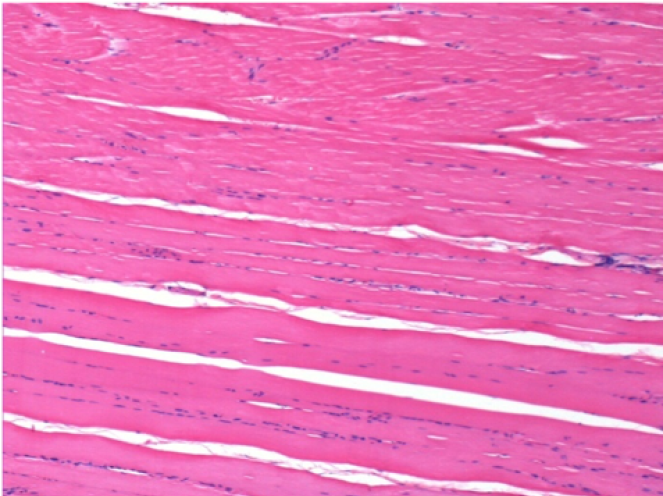

Л: Претибіальний м'яз - без лікування